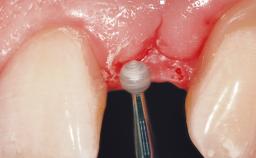

A 29-year-old female patient presented for treatment to replace the upper left central incisor tooth with an implant- supported restoration. The tooth had been intermittently symptomatic for the previous 12 months. The tooth had originally suffered trauma about 15 years previously. Several endodontic treatments had been performed, including an apicectomy procedure to retain the tooth. The patient was healthy and a non-smoker. She had reasonable expectations in regard to esthetic outcomes and the risk of marginal tissue recession following treatment. At medium smile, the gingival margins of the upper teeth were visible, with a display of 3 to 4 mm of the gingival margins. Gingival recession of tooth 21 and a discrepancy in the gingival levels between teeth 11 and 21 was observable during normal speech and smile.

| Soft Tissue Contour and Volume | Slightly compromised |